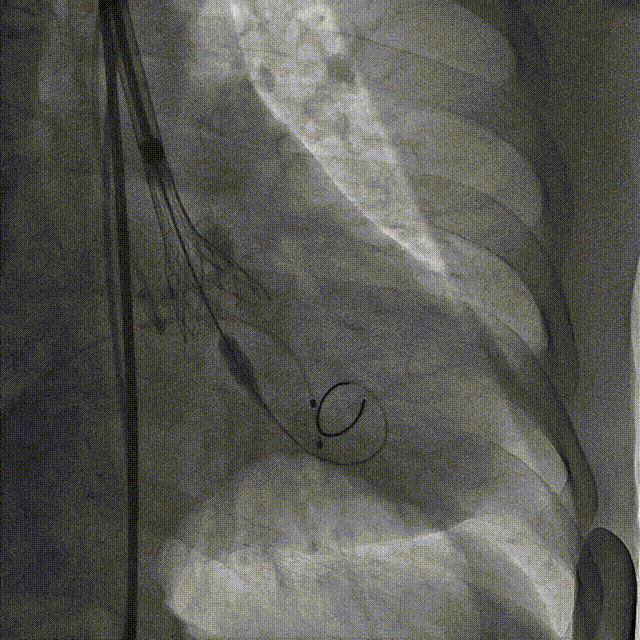

4.瓣膜第一次释放下滑明显,第二次初始定位瓣上2mm,缓慢释放开花,提拉输送器,快速释放到工作位,造影显示位置良好,少量瓣周漏,决定脱钩

第二次瓣膜初始定位及释放

第二次瓣膜脱钩

5.瓣膜释放后造影显示位置良好,冠脉未见遮挡,少量瓣周漏,超声提示瓣膜植入后活动良好,少量瓣周漏,导管测压提示压差2mmHg,造影检查入路血管,无造影剂外渗,手术顺利结束。